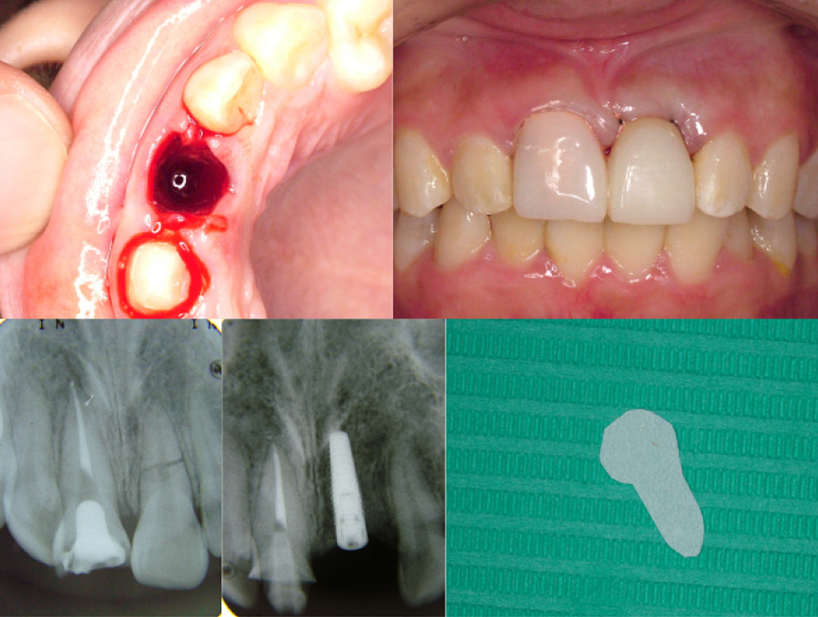

治療前治療後

| 治療内容 | インプラント奥歯1本・根管治療・矯正治療(圧下) |

|---|---|

| 患者様の年齢 | 40歳 |

| 患者様の性別 | 男性 |

| 治療期間 | 1年 |

| 治療回数 | 矯正治療合わせて50回程度 |

| 治療費用 | 根管治療1歯6万円/インプラント治療1歯50万円 矯正治療:1歯 10万円 |